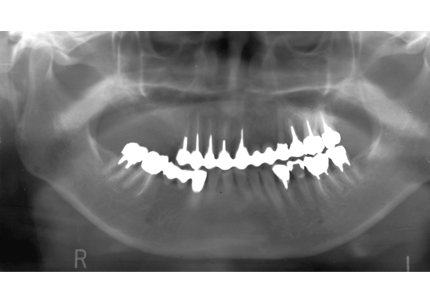

8.初診より現在に至る

強い歯ぎしり、くいしばりで奥歯の歯牙破折、深い虫歯で保存不可能となり全顎治療となる。

↑ 2007年6月30日(初診)